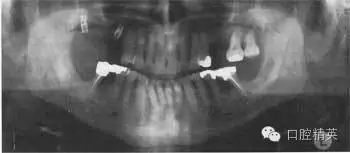

圖38.2 患者牙齒的全口牙位曲面體層X線片

牙齒全口牙位曲面體層X線片如圖38.2所示,你看到了什么?

答:全口牙位曲面體層X線片不是很清晰?;颊哳^位沒擺正,使圖像產(chǎn)生很大扭曲。下頜骨下緣呈彎曲圖像,且下前牙被縮短了。因?yàn)轶w位不正,脊柱陰影也被增強(qiáng)了。因?yàn)橛跋裰丿B,中線處的牙齒沒在中點(diǎn)。頭偏向一邊,一側(cè)影像被放大。這在后牙牙冠上很容易看出來,因?yàn)橛覀?cè)比左側(cè)的牙冠大?;颊叩男g(shù)后片如圖38.3,它顯示了正常片子應(yīng)顯示的樣子。

X線片顯示,了右下及左下第二磨牙周圍廣泛的骨質(zhì)破壞。左下第二磨牙有骨喪失并有根分叉處齲壞。下頜兩個(gè)第一磨牙有明顯的根分叉病變,但卻不松動。